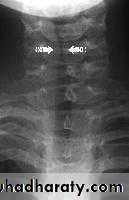

Anteroposterior X-ray of the neck shows subglottic narrowing (steeple sign).

Steeple sign (Croup) Thumb sign (Epiglottitis)